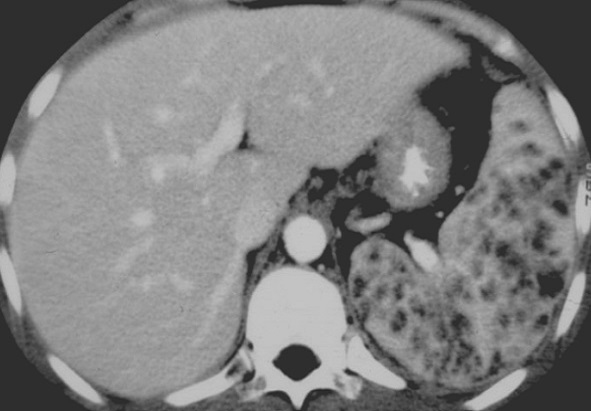

La lesion de abces fungique se presence

au rate sous forme des micro-abces arrondie ou

ovalaire hypodensite diffusant . Ces lesions peuvent

en s.observent encore dans le foie . Image

radiologique TDM plus C+ intraveineuse , coupe

axiale |